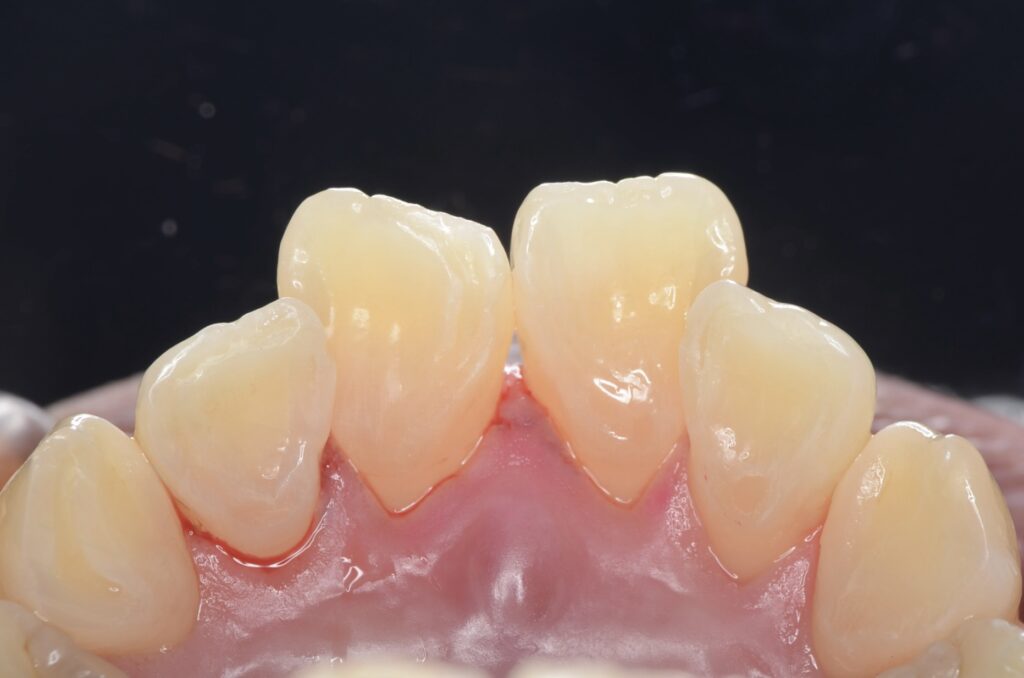

60代 審美治療 ジルコニアクラウン・虫歯治療 ダイレクトボンディング#55

Before

After

| 年齢 | 60代 | 治療方法 | ジルコニアクラウン/ダイレクトボンディング |

|---|---|---|---|

| 性別 | 女性 | 通院回数 | 6回 |

| 主訴 | 前歯を綺麗にしたい・歯を削る量を少なくしたい | 費用 | 308,000円(税込) |

| 治療のメリット | 歯を削る量を少なくできる・自然な見た目・境目がピッタリできる | ||

| 治療のデメリット | 大きい虫歯治療には適応できない場合がある | ||